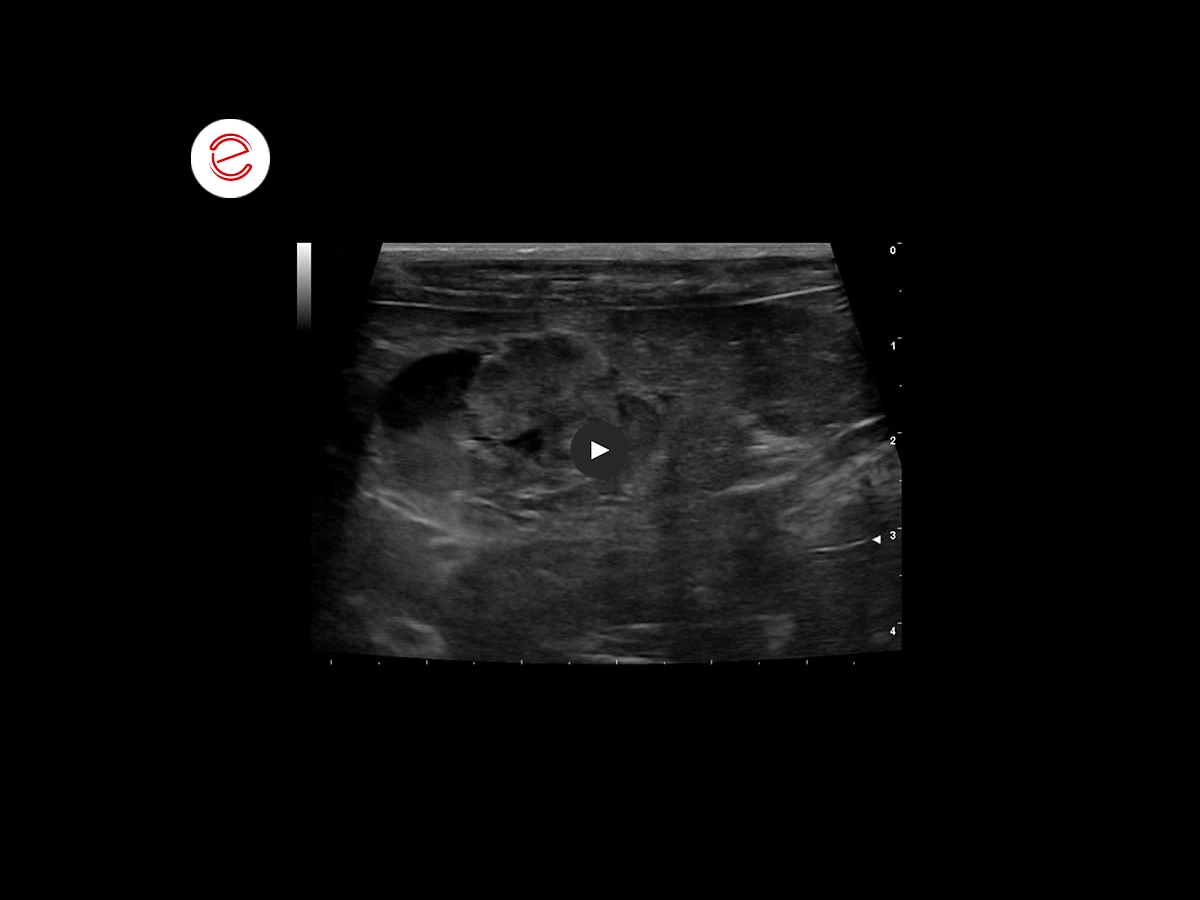

The two-dimensional ultrasound examination shows a hyperechoic neoformation with an inhomogeneous echo structure projecting into the lumen of the gallbladder.

In this image, the neoformation with relative dimensions of 1.60 x 2 cm is observed.